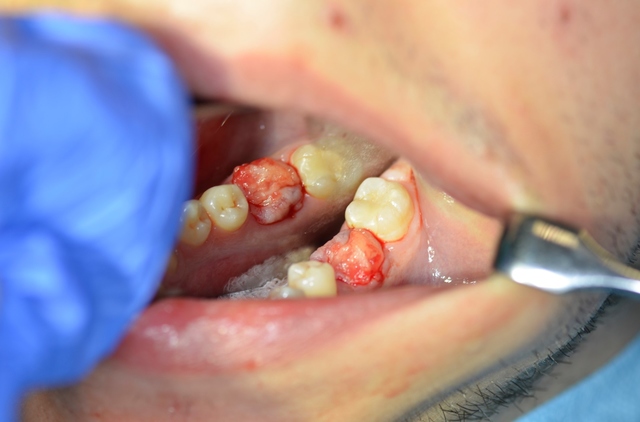

W znieczuleniu miejscowym przeprowadzono minimalnie inwazyjny zabieg usunięcia zęba metodą separacji korzeniowej. Następnie założono szablon implantologiczny i używając systemowej sekwencji wierteł, wypreparowano łoże pod wszczep, który następnie wprowadzono, uzyskując stabilizację pierwotną; zabezpieczono go śrubą zamykającą (Implant Seven, MIS). Wolne przestrzenie zębodołu poekstrakcyjnego wypełniono materiałem kościozastępczym (Bio-Oss, 0,25-1 mm, Geistlich Biomaterials, Szwajcaria), a całość pokryto błoną z osocza bogatopłytkowego oraz lateksowym koferdamem, utrzymywanymi szwami, które pozostawiono na 7 dni (ryc. 7-13).

Wykonano pantomogram oraz zdjęcie celowane, które ujawniło zmianę okołowierzchołkową przy korzeniu dystalnym. Nie stwierdzono patologii tkanek twardych zębów sąsiadujących z zębem zakwalifikowanym do ekstrakcji, dlatego powzięto decyzję o odbudowie implantologicznej przyszłego braku zębowego (ryc. 1-3).